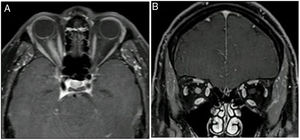

Neuritis óptica (figs. 2 y 3), que suele ser extensa, con compromiso del quiasma óptico o más del 50% de la longitud del nervio óptico y con un compromiso de moderado a severo de la agudeza visual.

Las lesiones medulares por NMO son longitudinalmente extensas, es decir, comprometen tres o más segmentos medulares contiguos, y transversas o centromedulares, por lo que generan paraparesia o cuadriparesia asociada con síndromes sensitivos medulares, según el nivel de la lesión28.